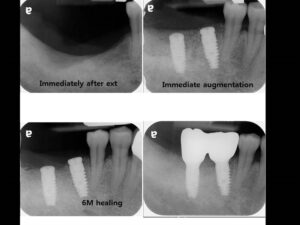

Етапи імплантації зубів

Імплантація зубів – процедура, що вимагає суворого дотримання встановленого протоколу лікувально-діагностичних заходів, що включає кілька етапів імплантації зубів. Кількість і характер етапів імплантації можуть відрізнятися в залежності від початкового стану зубощелепного апарату пацієнта, а також обраного виду і методики проведення самої процедури установки імплантів – одно або двоетапної.

Двоетапна методика є найбільш надійною і прогнозованою, вона відрізняється дуже високими показниками приживлюваності імплантатів (97-98%), а встановлені з її використанням штучні зуби можуть прослужити 15-20 років, а нерідко і довше. Процедура встановлення дентальних імплантів по двоетапній методиці можна виділити 3 основних етапи імплантації:

На цьому етапі імплантації здійснюється установка самого імпланту і формувача – перехідника між кореневою частиною імпланта і його супраструктурами. Таким чином, в хірургічному етапі можна виділити два проміжних етапу імплантації:

- Установка імпланта.

- Установка формувача.

При використанні класичної двоетапної методики імплантації спочатку встановлюється сам імплант і лише після його повного і остаточного приживлення на ньому через перехідник (формувач) фіксується супраструктура – коронка або міст. Проміжок між цими двома етапами імплантації становить кілька місяців.

Десна надрізається по гребеню альвеолярнго відростка і відшаровується слизисто-окисний клаптик, щоб створити необхідне поле для роботи хірурга-імплантолога. Далі за допомогою фрез різного діаметру (від меншого до більшого) висвердлюється канал потрібного діаметру і глибини – формується кісткове ложе для штучного кореня. У це ложе встановлюється імплант на необхідну глибину: гвинтові конструкції вкручуються, циліндричні встановлюються незначною натяжкою.

Коли імплант встановлений, в нього вкручують заглушку, яка захищає його від механічних впливів, а також запобігає інфікуванню кісткового ложе і проростання тканин в отвір для гвинта. Після цього слизисто-окисний клаптик укладається на своє колишнє місце, а розріз щільно зашивається. На цьому перший хірургічний етап імплантації закінчується.

Далі йде «перерва», необхідна для надійного приживлення імпланта. Кісткова тканина нижньої щелепи, більш щільна і об’ємна, для цього потрібно 2-3 місяці, в менш щільній губчастій кістці верхньої щелепи він приживається 4-6 місяців.

Коли коренева частина імпланта надійно прижилася, на неї встановлюється формувач, вірніше два його різновиди, які ставляться по черзі. Спочатку встановлюється абатмент, що виконує роль формувача ясен, щоб створити її чіткий рівний контур, не відрізняється від ясенного краю «рідних» зубів. Для цього замість заглушки встановлюється формувач ясен, який виступає над нею на кілька міліметрів. Формування ясенного краю сягає близько 2 тижнів.

Через 2 тижні формувач ясен видаляється і на його місце встановлюється постійний абатмент. За допомогою абатмента можна буде при необхідності відрегулювати довжину коронкової частини імпланта і кут його нахилу. Для цього використовуються абатменти різної довжини і з різним кутом нахилу, що дозволяє максимально точно «вписати» імплант в зубний ряд.